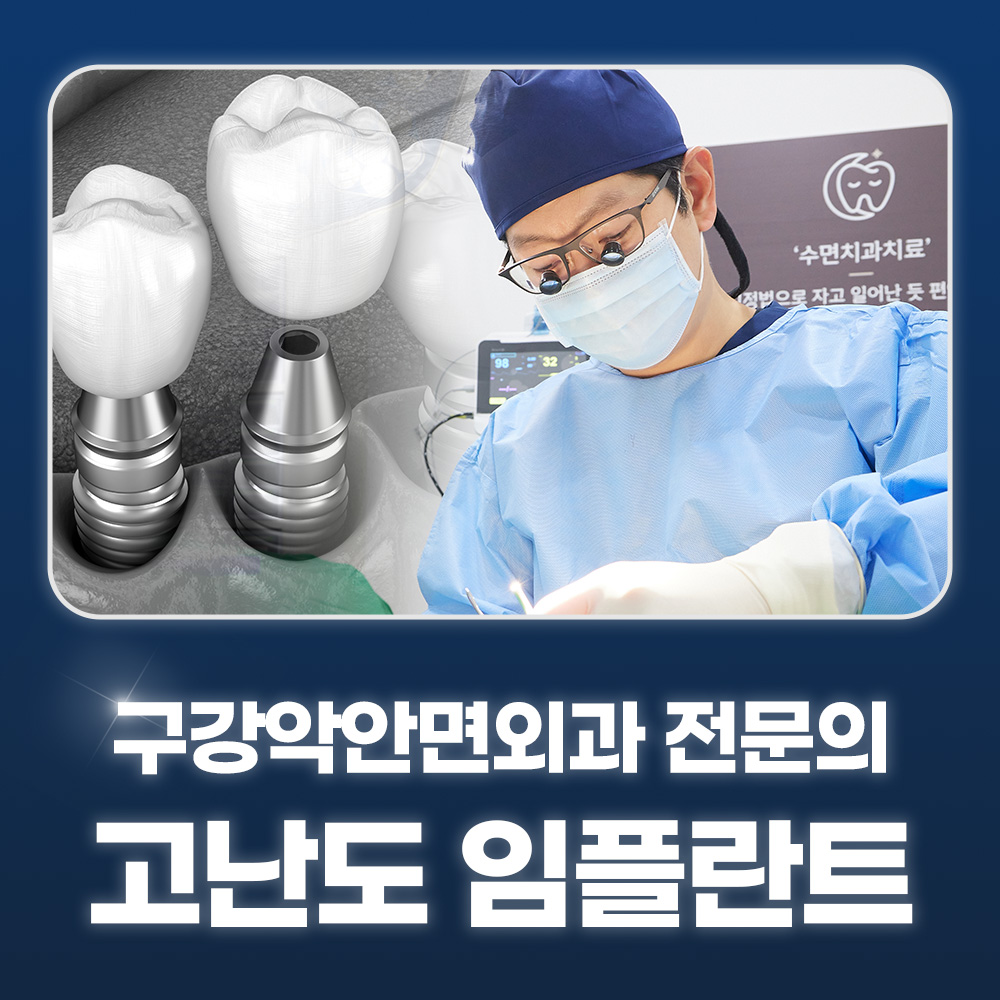

수술 담당 구강악안면외과 전문의

고난도 수술 진료

임플란트와 사랑니 발치는 외과적 시술로 잇몸을 절개하는 외과적 시술은

짧으면 짧을 수록 시술 후 붓기와 통증이 최소화됩니다.

치과의사 경력 14년차 구강외과 전문의가 빠르고 안전하게, 아프지 않게 수술해 드립니다.

치과경력 14년차 구강외과 전문의

연세대학교 치과대학 구강외과 임상 조교수

빠른 수술 / 적은 통증